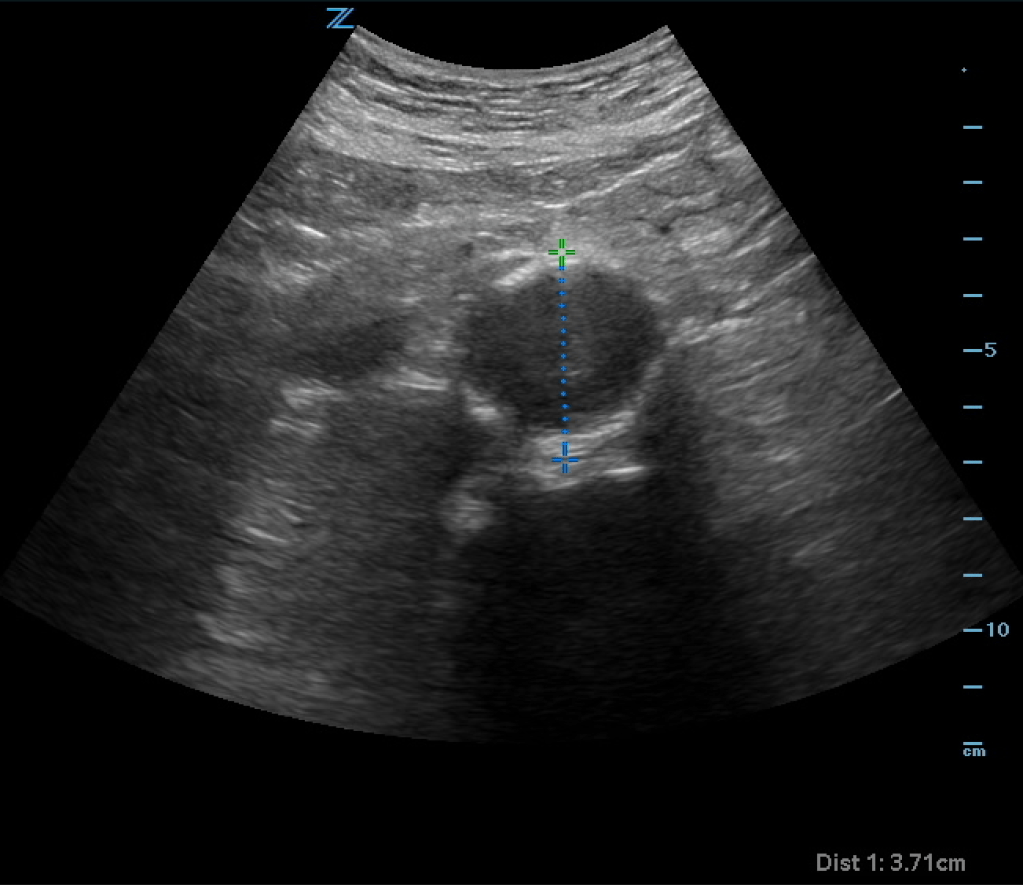

You obtain a bedside ultrasound:

The ultrasound shows an enlarged aorta concerning for AAA, measuring at 3.71cm. However looking closely at the aorta, it almost appears as if there is a dissection flap with potentially two lumens on the ultrasound. You obtain color doppler: